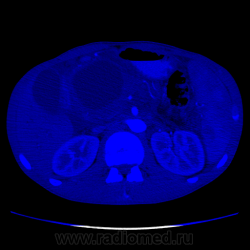

Видео крутит быстро. В головке плджелудочнгой железы кистозное образование с неравномерной толщины капсулой, наличием перегородок и солидного компонента. Печёночные желчные протоки, холедох значительно расширины. Вирсунгов проток расширен. Начальные отделы воротной вены сужены, возможно есть прорастание, не могу уследить. Итого: макрокистозная цистаденома (возможно уже цистаденокарцинома)

Не вижу, честно говоря, ни перегородок, ни солидного компонента. Вижу несколько (кажется, 3, но крутит очень быстро) кистозных образования в головке поджелудочной с относительно равномерно утолщенной капсулой. Плюс - неравномерное расширение Вирсунгова протока, инфильтрация перипанкреатической клетчатки и выпо в брюшной полости. Все укладывается в картину хронического панкреатита в стадии обострения с образованием псевдокист в головке железы.